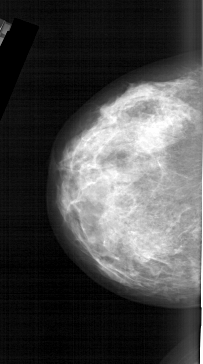

A_1566_1.LEFT_CC

LEFT_CC LINES 6181 PIXELS_PER_LINE 3451 BITS_PER_PIXEL 12 RESOLUTION 43.5 NON_OVERLAY